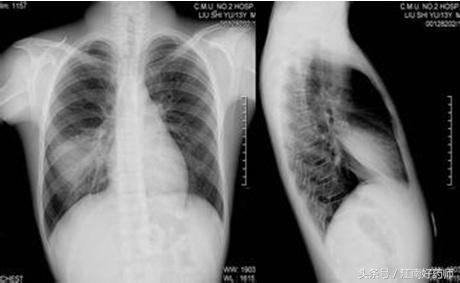

5.肺炎所伴随咳嗽

起病突然,伴随有高热、寒战、胸痛、吐铁锈色痰。